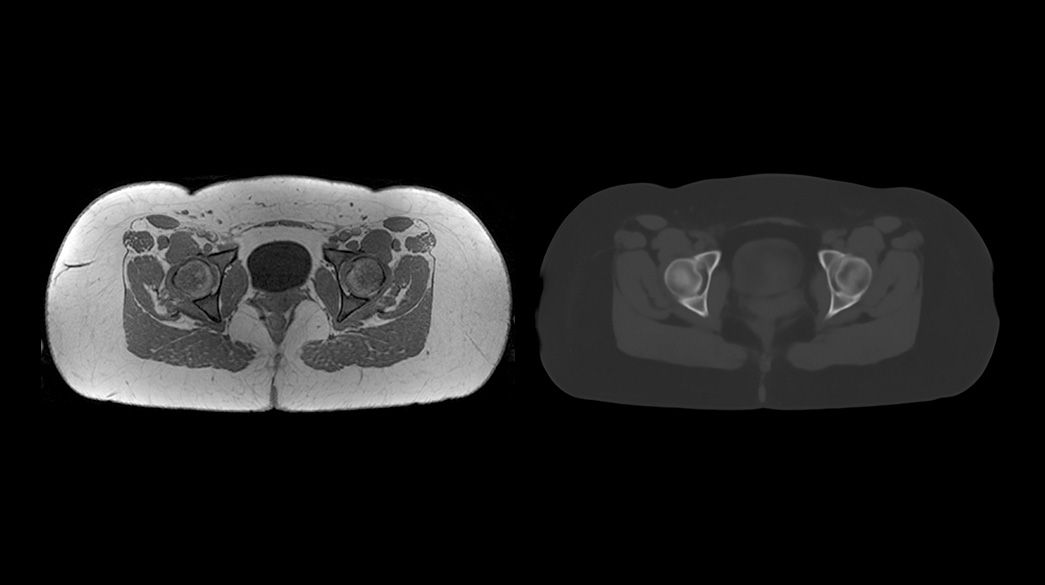

Oncology MR imaging techniques to capture anatomical and morphological data with robust tissue contrast, motion-insensitive and high temporal and spatial resolution for oncological assessment.

Advanced-DWI1040-x-585

Read case study ico-caret-right